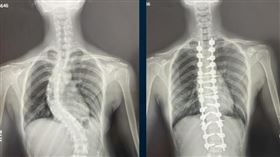

脊椎側彎長短腳佔大宗 醫師教你如何選鞋

很多脊椎側彎的原因其實是在「長短腳」,北市聯醫中興院...